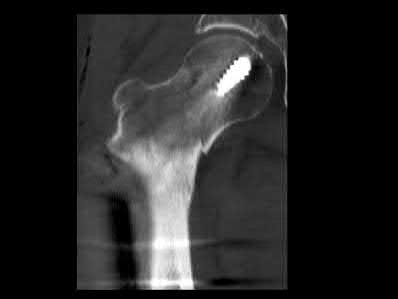

A 76-year-old male community ambulatory presented to clinic complaining of pain in the left groin that has been persistent for the last 8 months. Radiographs obtained from clinic are seen in Figure A. You suspect a femoral neck nonunion and obtain a CT scan which confirmed it. Which of the following statements is true?

A total hip arthroplasty (THA) after nonunion of a femoral neck fracture would provide the best long term outcomes in a 76-year-old male who is a community ambulator.

After nonunion of a femoral neck fracture, hemiarthroplasty and THA are good salvage option for the physiologically older patients. When deciding between these two options, THA is better for active and cognitively intact patients. THA is also indicated in patients with radiographic evidence of degenerative disease about the acetabulum. Hemiarthroplasty is advocated for patients who are older and less active.

Yang et al. retrospectively investigated the risk factors for nonunion in patients treated with cannulated screws. They reviewed 202 patients who had femoral neck fractures and were treated with internal fixation with cannulated screws. They identified that triangle configuration, displaced fracture, borderline or unacceptable reduction, and increased screw shaft subchondral purchase over the femoral neck were all risk factors for nonunion after internal fixation.

Inverted triangle configuration was found to increase rate of union.

Archibeck et al. retrospectively reviewed the outcomes of 102 THAs after failed internal fixation for a hip fracture (including both femoral neck and intertrochanteric). They concluded that the conversion of failed hip internal fixation has elevated risks compared to a primary THA, however, it may still be successful. The biggest concern for these patients postoperatively are periprosthetic fracture and dislocation.

Figures and Illustrations:

Figure A is an AP pelvic radiograph demonstrating a nonunion of a femoral neck fracture after suboptimal fixation with 3 cannulated screws in a triangle configuration.

Illustration A is an AP radiograph of the left hip in this patient following conversion to THA.

Illustration B is a radiograph demonstrating a valgus osteotomy. Illustration C shows an example of a femoral neck nonunion with varus malreduction.